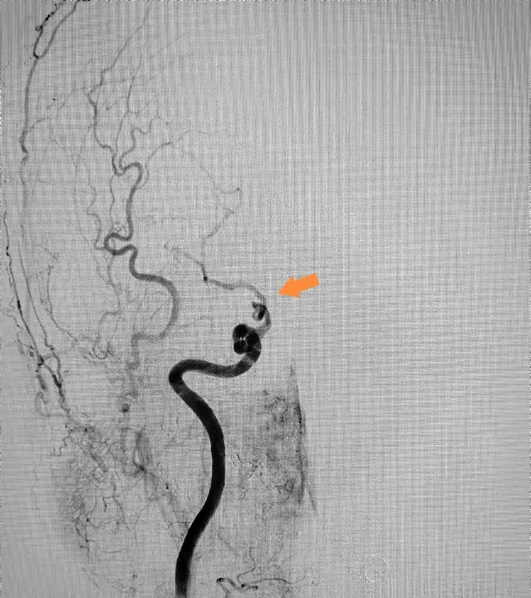

术后DSA

“时间就是大脑”,治疗每延误1分钟,将有190万个脑细胞死亡,等不来、缓不得、也拖不起,轻则导致偏瘫、失语,重则导致死亡。左大爷被送往手术室后,纪文军主任医师带领介入治疗团队立即对他进行了全脑血管造影术检查,术中进一步确诊患者的右侧颈内动脉末端完全闭塞,远端血管不显影。随后,由纪文军主任医师主刀,在李涛副主任医师和郭谢凡住院医师配合下,应用国内先进的抽吸+支架结合取栓,用快的速度使闭塞的右侧颈内动脉实现了再通,再次造影显示右侧颈内动脉血供恢复通畅,达到血流三级再通。手术过程非常顺利。